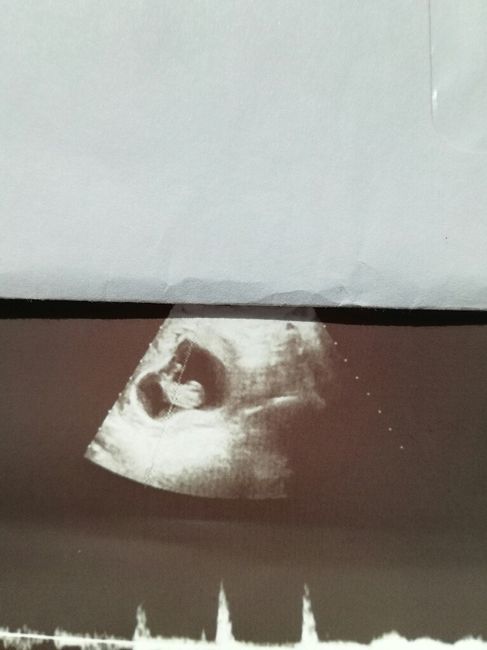

Ecografia e utero retroverso

Da Valentina , Il 5 Maggio 2017 alle 16:17

Oggi ho fatto l'ecografia ed ecco a voi il nostro fagiolino _love_) ...